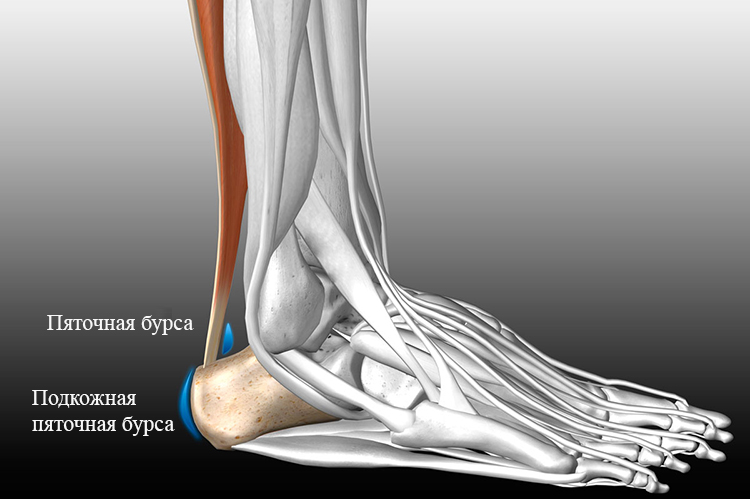

Тендинит Ахиллова сухожилия: симптомы и лечение

Раздел: Картинки на заметку